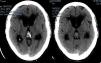

Presentamos el caso de una paciente de 72 años de edad sin antecedentes de interés que consultó en urgencias por un cuadro de 2 semanas de evolución de alteración de la marcha, cefalea y vómitos. El TAC craneal reveló la presencia de hidrocefalia obstructiva secundaria a una lesión pineal con impronta en el tercer ventrículo. La resonancia magnética mostró, además de la lesión ya referida, otra más pequeña situada en el foramen de Lushcka derecho. Se llevó a cabo una ventriculostomía endoscópica del suelo del tercer ventrículo y la biopsia endoscópica de la lesión, cuyo resultado fue de metástasis compatible con carcinoma de pulmón. Se realizó un TAC toracoabdominopélvico que mostró una masa pulmonar compatible con el carcinoma primario. Se decidió tratamiento sistémico de la enfermedad. La paciente falleció 2 meses tras el diagnóstico.

A 72-year-old female with no relevant medical history consulted in the emergency room for a two-week history of headache, vomiting and gait disturbance. Head CT scan revealed obstructive hydrocephalus secondary to a pineal mass with compression of the third ventricle. Magnetic Resonance showed another mass located in the right Lushcka foramen. Endoscopic third-ventriculostomy and biopsy of pineal mass were performed. Pathological analysis was consistent with metastasis of carcinoma. Full-body CT scan showed a lung mass related to primary carcinoma. The patient received systemic treatment for metastatic lung cancer. She died two months after diagnosis.